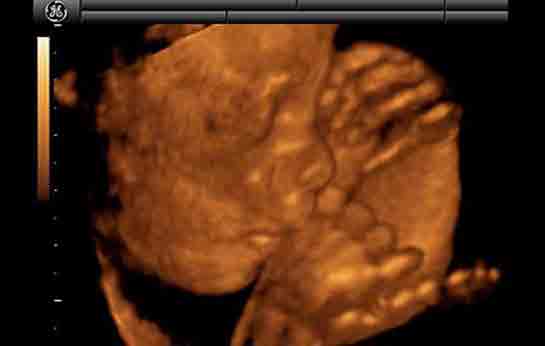

30 haftalık gebelik, hamileliğin üçüncü trimesterinin başlangıcını işaret eder ve bu dönemde hem anne hem de bebek için önemli değişimler ve gelişmeler yaşanmaktadır. Gebelik süreci, fetal gelişim, anne sağlığı ve doğum süreci açısından kritik bir zaman dilimidir. Bu makalede, 30 haftalık gebelik döneminin fiziksel, duygusal ve sağlık açısından önemli yönleri ele alınacaktır. Fetal Gelişim30. haftada, fetüs büyük ölçüde gelişimini tamamlamış durumdadır. Bu dönemde fetüsün büyüklüğü ve gelişimi aşağıdaki gibi özetlenebilir: